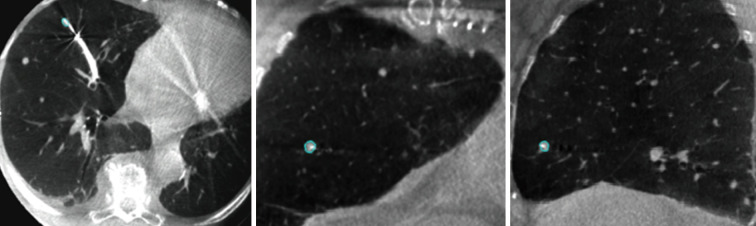

CBCT was used in all ENB and ssRAB procedures similarly. Prior to navigating to the nodule, time was taken to isocenter the patient with CBCT (Philips Allura Biplane with Lung Suite software; Philips, The Netherlands). Once navigational success was suspected, a biopsy tool was inserted followed by an 8-second CBCT spin, performed under breath-hold with adjustable pressure-limiting valve set at 20 cmH2O, to decrease the degree of respiratory motion and atelectasis during the spin. Airway segmentation for the target lesion in multiple orthogonal planes (Figure 1) was done and superimposed on live fluoroscopy using dedicated software (Philips Lung Suite software). Based on tool tip location, catheter adjustments were performed under live fluoroscopy as needed. Augmented fluoroscopy is shown in Figure 2. Once tool in lesion was confirmed, biopsies were taken under similar breath-hold.

Figure 1.

Cone-beam computed tomography images in axial, coronal and sagittal views of a 5 mm × 3 mm nodule with needle in lesion confirmation.